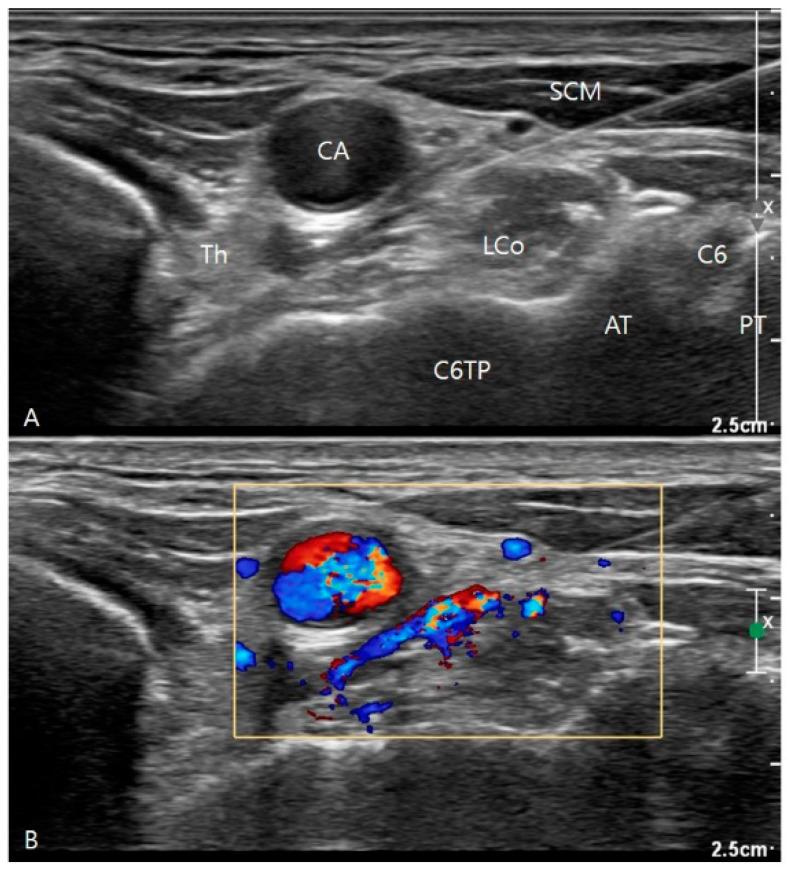

Post-stroke complex regional pain syndrome (CRPS) poses challenges in pain assessment for survivors. Stellate ganglion block (SGB) is a treatment, but evaluating its effectiveness is difficult for patients with communication limitations. Edema, a prominent symptom, can serve as an evaluation marker. Bioelectrical impedance analysis (BIA), assessing body composition and fluid status, is used independently of patient cooperation. This retrospective, observational pilot study aims to explore BIA's utility as an assessment tool post-SGB, revealing the effects and time courses of a single SGB on the bodily composition of post-stroke CRPS patients. Seven patients received ultrasound-guided SGB with a 5 mL solution containing 4 mL of 0.25% bupivacaine hydrochloride and 40 mg of triamcinolone into the prevertebral muscle space. BIA compared measures between affected and unaffected arms. The affected arm had higher segmental body water (SBW) and extracellular water ratios before SGB ( = 0.028 and = 0.018, respectively). The SBW of the affected side, the SBW ratio, and the 1 and 5 kHz SFBIA ratios improved over time ( = 0.025, 0.008, 0.001, and 0.005, respectively). Rapid improvement occurred around 3 days post-injection, with maximum effects within approximately 1 week, persisting up to 3 weeks. SGB successfully reduced edema in post-stroke CRPS patients, with BIA serving as a useful tool for follow-up, facilitating the development of efficient treatment plans.

中风后复杂性区域疼痛综合征(CRPS)给幸存者的疼痛评估带来了挑战。星状神经节阻滞(SGB)是一种治疗方法,但对于存在沟通障碍的患者而言,评估其有效性较为困难。水肿是一个突出症状,可作为评估指标。生物电阻抗分析(BIA)用于评估身体成分和液体状态,其使用无需患者配合。这项回顾性观察性试点研究旨在探讨BIA作为SGB后评估工具的效用,揭示单次SGB对中风后CRPS患者身体成分的影响及时间进程。7例患者接受了超声引导下的SGB,将含有4 mL 0.25%盐酸布比卡因和40 mg曲安奈德的5 mL溶液注入椎前肌间隙。BIA比较了患侧和未患侧手臂的测量值。在SGB前,患侧手臂的节段性身体水分(SBW)和细胞外水分比率较高(分别为 = 0.028和 = 0.018)。患侧的SBW、SBW比率以及1 kHz和5 kHz的SFBIA比率随时间改善(分别为 = 0.025、0.008、0.001和0.005)。注射后约3天出现快速改善,在约1周内达到最大效果,持续至3周。SGB成功减轻了中风后CRPS患者的水肿,BIA作为随访的有用工具,有助于制定有效的治疗方案。